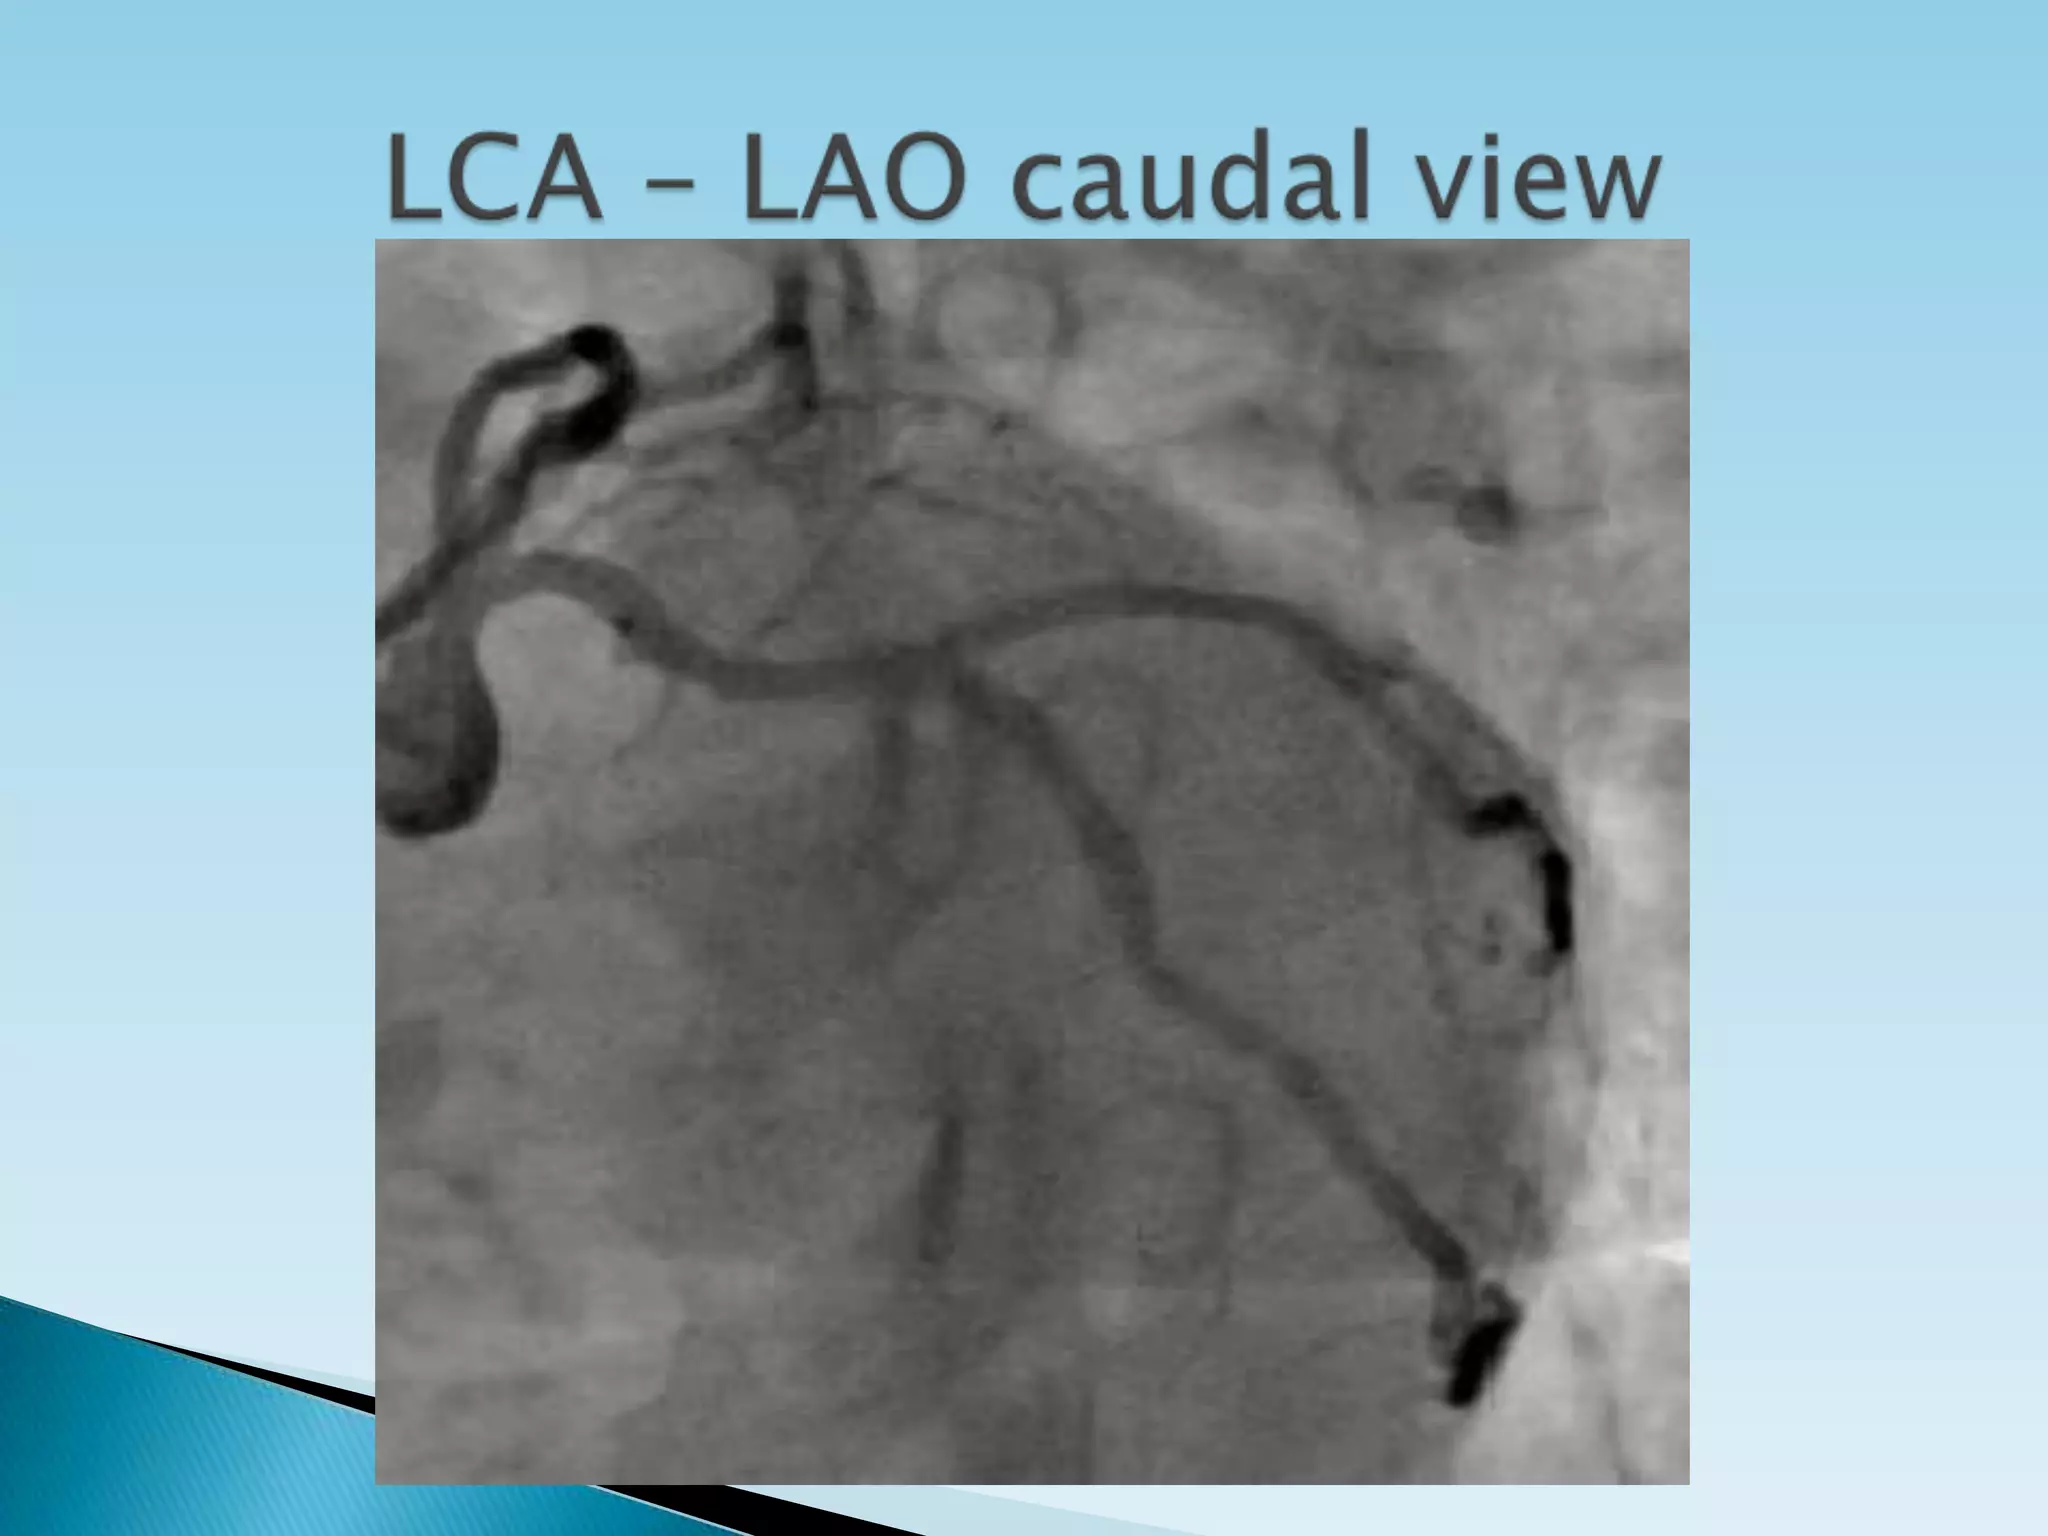

   Generally, for circumflex and proximal

epicardial visualization the caudal views are

most useful.

 Left   Main        AP, LAO cranial, LAO caudal

Proximal circumflex   RAO cranial, LAO caudal

Intermediate          RAO caudal,LAO caudal

Obtuse marginal       RAO caudal, LAO caudal, RAO